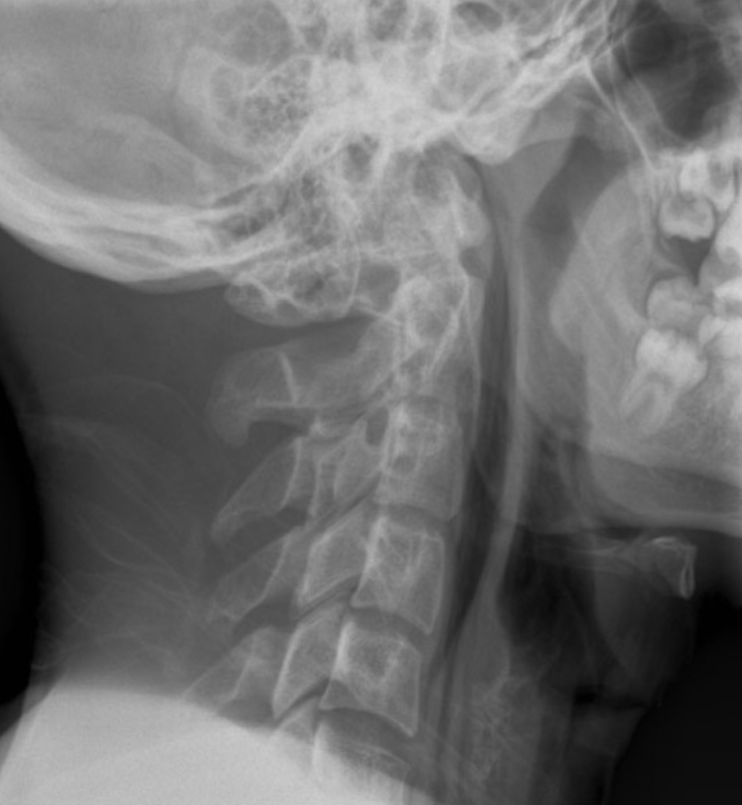

A young male comes to the ED with severe pain in his neck and upper chest. It came on suddenly after he had fish and chips earlier that evening. No significant previous history.

retropharyngeal air ( crescentic air anterior to the vertebral bodies)

surgical emphysema